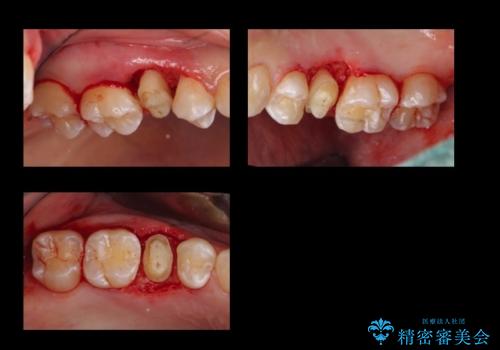

角化歯肉の幅がしっかり合ったため、歯肉をずらすAPF(アピカリ)でなく、切除療法を行いました。

骨外科の量は多かったですが、術直後見られた動揺も治っています。

術後の痛みへの対処は、鎮痛薬を服用していただきます。